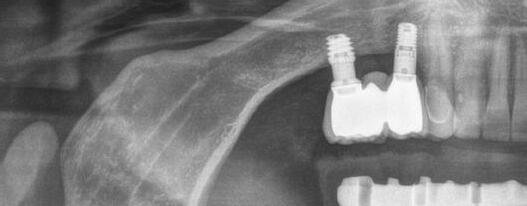

En las piezas 16 y 17 el paciente presentaba restauraciones atornilladas de metalcerámica sobre implantes oseointegrados. Se planificó realizar estas en una fase posterior a la rehabilitación de las piezas dentarias mediante flujo digital con bases de titanio y cuerpos de escaneo.

Figura 5. Impresión digital, vista superior derecha. Figura 3. Escaneado maxilar superior zona anterior. Figura 4. Impresión digital, vista superior izquierda.